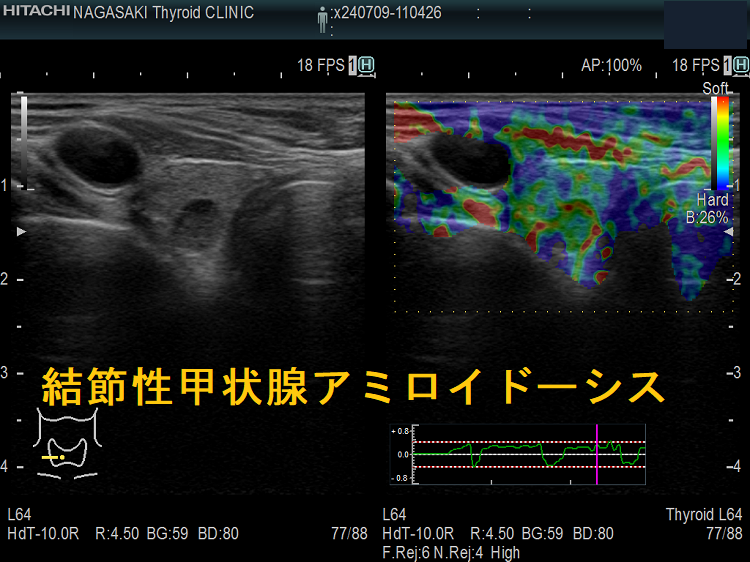

謎の結節性甲状腺アミロイドーシスを鹿児島大学が甲状腺学会で複数回、さらに大分大学も論文で報告しています。超音波(エコー)検査上、見かけは甲状腺腫瘍、境界不明瞭・不均質な低エコー領域で、石灰化も伴う。穿刺細胞診で腫瘍成分はなく、アミロイドのみが見つかるも、アミロイドーシスをおこす他の病気が全くないとの事です。

橋本病に合併した結節性甲状腺アミロイドーシスの病理組織標本では、

- アミロイド結節内の甲状腺濾胞構造は破壊され、異物反応や石灰化も存在する(第57回 日本甲状腺学会 P2-061 橋本病に合併した甲状腺amyloidosis の一例)

- アミロイド結節周囲の甲状腺組織には、リンパ球・形質細胞の炎症性細胞浸潤とリンパ濾胞形成を認めます。これらのリンパ球・形質細胞が、IgGのκ鎖を産生するのが原因では?と推察しますが、原因不明です。(第58回 日本甲状腺学会 P1-12-3 橋本病に合併した甲状腺限局免疫グロブリン軽鎖amyloidosisの一例)

- アミロイド沈着物は、細胞質内に小アミロイド滴を含む多数の組織球と多核巨細胞に囲まれる。しかし、血管壁にアミロイド沈着は無し。免疫組織化学検査により、アミロイドはアミロイドP成分、IgG、κ軽鎖が強陽性で、IgG、特にκ軽鎖(AL)が前駆体タンパク質と判明。[Acta Pathol Jpn. 1992 Mar;42(3):210-6.]。